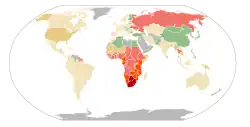

Demência na doença pelo vírus da imunodeficiência humana ou Doença pelo HIV resultando em encefalopatia se refere a uma degeneração cerebral que se desenvolve no curso da doença pelo HIV, mesmo na ausência de qualquer outra doença ou infecção simultânea que possa explicar a presença das características clínicas.[1] Com a invenção da terapia antirretroviral altamente eficaz (TARV) os casos de demência na AIDS diminuíram entre 30-60%.[2]